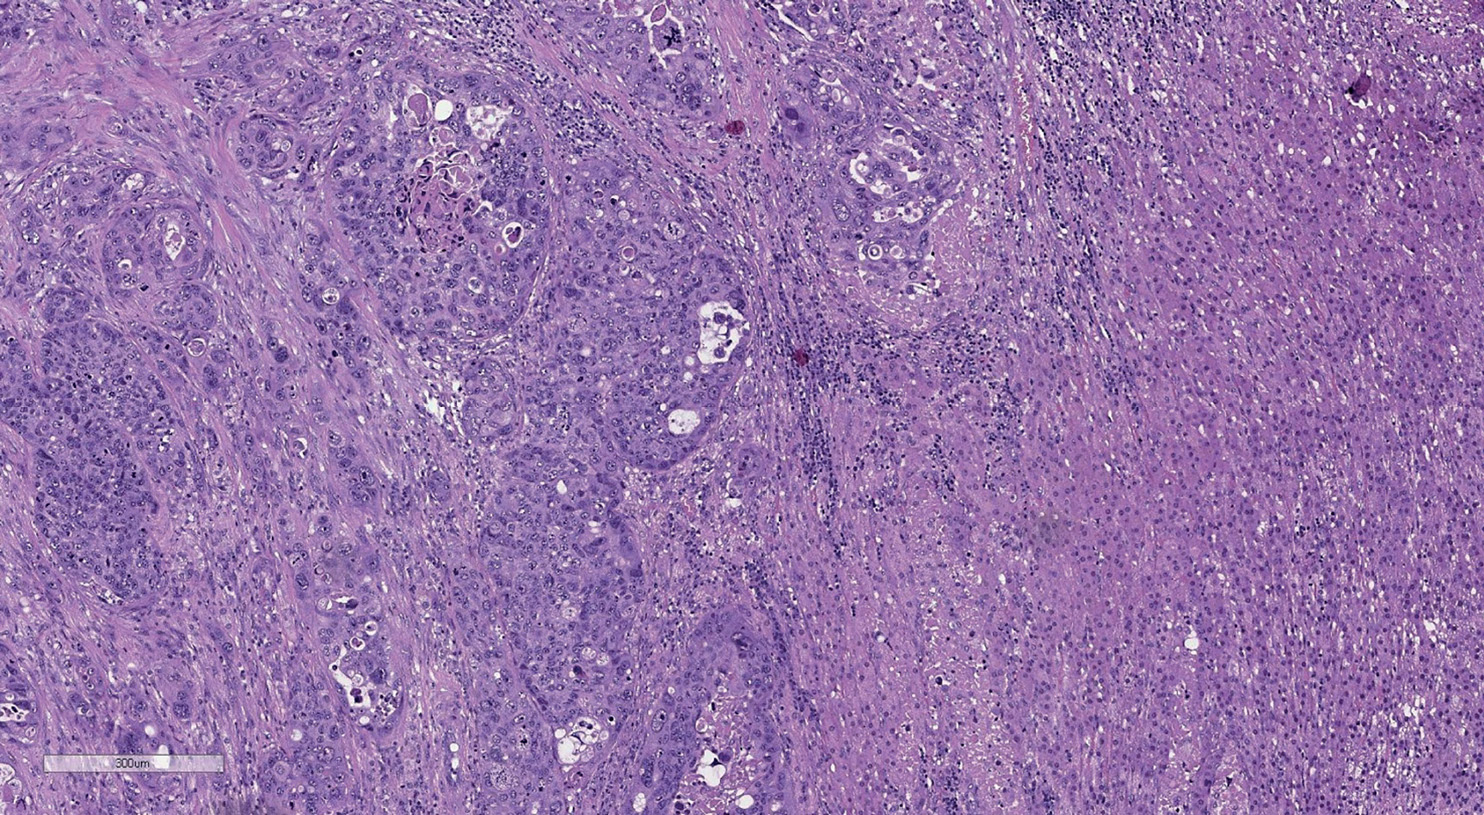

Differentiation between benign, primary and secondary malignant tumors is a critical problem in the clinical treatment of adrenal tumors, especially in patients with isolated adrenal lesions. In most cases, the correct diagnosis can be established microscopically with standard staining with hematoxylin and eosin. However, there are cases when it is almost impossible to distinguish metastasis from primary adrenal cancer, so an accurate diagnosis requires an immunohistochemical examination.

This article presents five unique observations of secondary adrenal tumors that were diagnosed by us in the current surgical material: metastasis of clear cell renal cell carcinoma, follicular variant of papillary thyroid cancer, metastasis of keratinizing squamous cell carcinoma of the cervix, lymphoepithelioma-like carcinoma of the bladder, as well as malignant mesothelioma. Taking into account the extreme rarity of the presented observations, we present an analysis of the literature data.